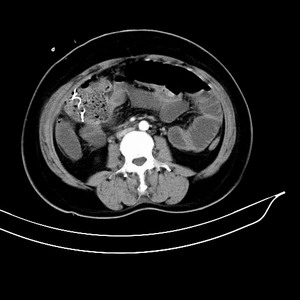

女 42岁 子宫肌瘤于外院术后两天,感腹胀。x线提示肠梗阻。

子宫肌瘤于外院术后两天,出现肠扭转梗阻,很明显。但右下腹部出现的线状高密度,是什么呢?有什么手术会有这样的物品呢?不会把电刀的导线遗留在腹腔吧!?

结果:术后纱布遗留,术后麻痹性肠梗阻肠梗阻

上面的图像是我们从手术室拿来的纱布做了个ct平扫,发现纱布里确实存在有一条致密影。后得知致密影是为防止手术时纱布遗留而设计。关腹时怀疑纱布遗留可做个床边透视或拍片可明确。